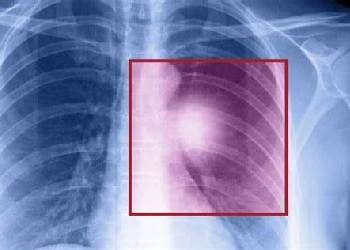

肺癌有多种基因突变,这些突变导致了肿瘤细胞异常生长,而靶向药的出现,让肿瘤治疗更加精准。靶向药阿法替尼是表皮生长因子受体(EGFR)和人表皮生长因子受体2(HER2)酪氨酸激酶的强效、不可逆的双重抑制剂。阿法替尼通过与EGFR和HER2结合,阻断这些受体在细胞内的信号传导,从而达到抑制肿瘤生长和扩散的目的。阿法替尼原研药来自德国,2017年获美国FDA批准上市,直到2017年2月阿法替尼才在国内上市,商品名为吉泰瑞。刚上市的马来酸阿法替尼片价格高达1万元左右,现如今阿法替尼医保价格多少钱?纳入医保降价后进口阿法替尼一盒的价格约为为1400左右,一盒是7片,一个月需要四盒的剂量,所以差不多一个月的价格大概在5600-6000元左右。效果一致的印度阿法替尼价格相对便宜,目前印度阿法替尼多少钱一盒一瓶?印度阿法替尼价格在2900-3000元一盒,一盒印度阿法替尼30片,可吃一个月。当今印度阿法替尼代购哪里买?

肺癌是一种复杂多变的疾病,其中非小细胞肺癌占据了约85%的病例。在这类肺癌中,常见的亚型有肺腺癌和肺鳞癌。研究人员发现,肺癌的发生和基因突变有着很大联系,其中表皮生长因子受体(EGFR)突变是一种常见的基因突变,尤其在肺腺癌中频率较高。对于亚裔非吸烟患者,EGFR突变的发生率更是高达40%至50%,而EGFR突变中又包括18位点G719X突变、19缺失突变、20位点S7681突变,21位点L858R突变、21位点L861Q突变等。这些位点对应使用的靶向药不同,例如亚洲不吸烟的女性,通常是19缺失突变和21位点L858R突变,此时使用易瑞沙、特罗凯、奥希替尼通常效果比较好,而肺鳞癌男性患者中,出现18位点G719X突变、20位点S7681突变、21位点L861Q突变等突变的情况比较多,此时使用阿法替尼效果比较好。